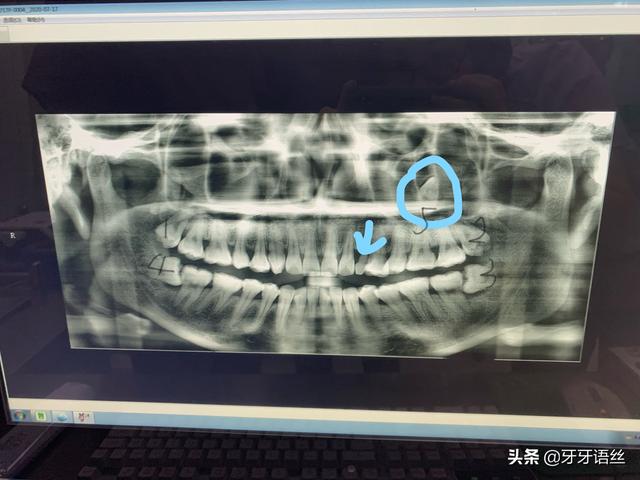

根据你所描述和图片所示,四个智齿都是需要拔除的适应症。上面的2个拔除的难度系数相对比较小,下面的2个拔除的难度系数比较大一点,需要牙龈切开、翻瓣、去除邻牙及骨的阻力、将智齿截断,然后分段去除,必要时还需要缝合;主持操作的医生需要较丰富的经验和较高的技巧。从所提供的图片上看,此案例的关键和难度是在题主没发现的地方,

如图所示,蓝色标识出来的是左上尖牙异位埋伏阻生在靠近左上颌窦的地方,这个才是难度大的所在。